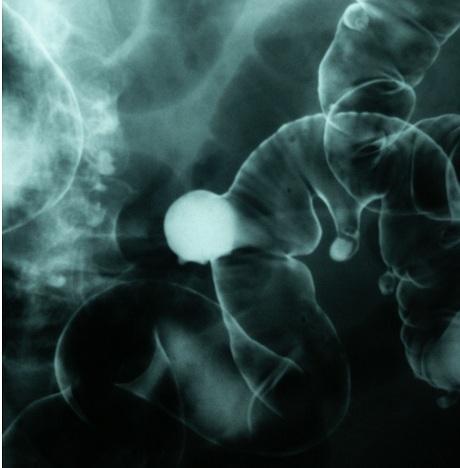

Actualmente el cáncer sigue siendo una de las principales enfermedades mortales en nuestra sociedad. Cuando se habla de cáncer no se hace referencia a una sola enfermedad sino a cada una de las cuales afecta a una parte distinta del organismo y que responde a una causa diferente.Todos los canceres dan lugar a alteraciones del organismo y generalmente dan señales de su desarrollo en forma de bulto. Éste es como un quiste que contiene miles de células cancerosas en su interior.La persona que sufre cáncer de intestino puede presentar estreñimiento, diarrea o ambas cosas a la vez y otros cambios en el funcionamiento normal del intestino. Además podemos encontrar sangre o pus en las heces, dolor de vientre, anemia, pérdida de peso y molestias de orden general.Es muy importante un diagnóstico correcto y temprano de esta patología porque en las primeras fases hay más probabilidades de éxito en la cirugía.Cualquier hemorragia del recto debe de examinarse con especial atención mediante un examen rectal. Aunque en la mayoría de los casos las hemorragias que tenga la persona puedan deberse a hemorroides.También es posible que la causa del cáncer intestinal sea debido a un consumo exagerado de grasas y a una dieta pobre en fibras vegetales.A continuación te contamos cómo tratar el cáncer de intestino.